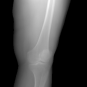

In this section, we provide qualitative and quantitative results of the two proposed diffusion-based methods and compare them with the baseline U-Net model. The first column of Fig. 3 showcases six randomly selected conditions: (a0)-(c0) show contour segmentations, and (d0)-(f0) denote segmentations containing contour and bones. In Fig. 3 (a1)-(f1), the images generated by U-Net contain blurred fine details in locations where bones overlap, despite maintaining the given shape, as highlighted by the red circle. In contrast, the results from CSM appear more realistic than the U-Net. However, their quality decreases with introduced constraints, as indicated by the red arrow in Fig. 3 (d2) and (f2). The results from CTM not only achieve nearly the same level of fineness as the labels but also provide reasonable results with respect to the given conditions as illustrated in the fourth column.